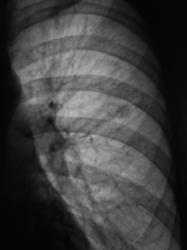

100.Rasshifrovka..jpg

Образование верхней доли левого легкого с дорожкой к корню, мне кажется может оказаться как периферическим раком ,так и туберкуломой.Надо начать с линейной томограммы. А нет ли вздутия переднего отрезка 3 ребра?

Этот дефект на всех снимках - это наше "факсимиле" - шутка. Дефект на экране, мы с ним уже смирились. Мы тоже подумали о периферическим раке и "дорожку" приняли к сведению. По поводу туберкулёза, как - то не подумали. Конечно, и о доброкачественной опухоли также вспомнили. Конечно, все "большие симпатии" в векторе периферического рака лёгкого.

И все таки похоже на туберкулому, мне кажется за год несколько уплотнилось образование, были более четкие,ровные контуры, а сейчас какбы чуть-чуть сжалось(или выдаю желаемое за действительное?). Просто у меня был очень похожий случай,только в нижней доле левого легкого за тенью сердца, с дорожкой к корню с лучистыми (как мне казалось)контурами образование чуть больше вашего,была уверена , что периферический рак, а больной сйчас в туб.диспансере лечит туберкулому.